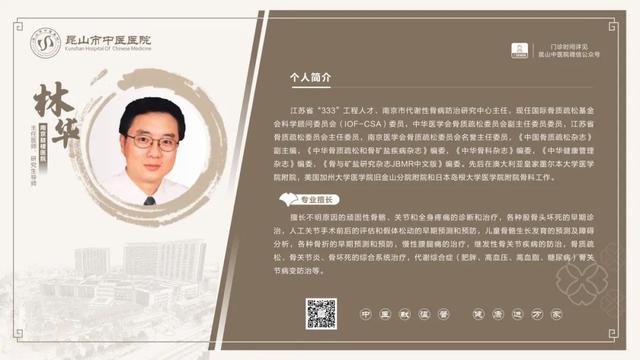

6��23��-6��29��������ר�ҳ���һ����

6��23��-6��29�������dz���ר�ҽ���